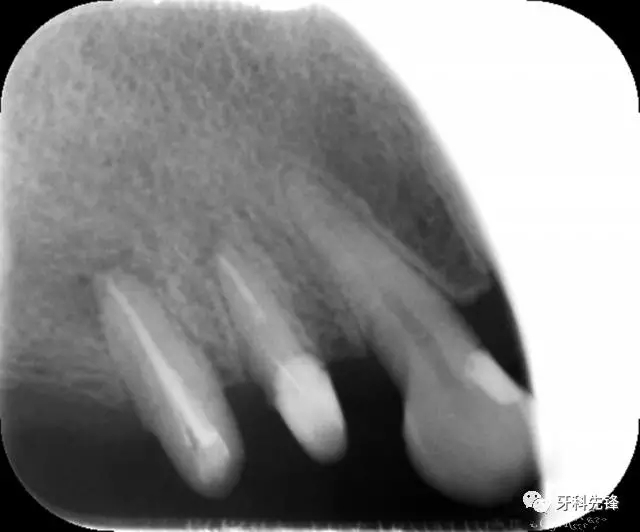

圖1 術(shù)前X光片

X 示:15  根管透射,根尖有陰影

14  根管阻射,恰填,無異常

46  根管阻射,恰填,根分叉骨密度降低,近中根尖陰影較大